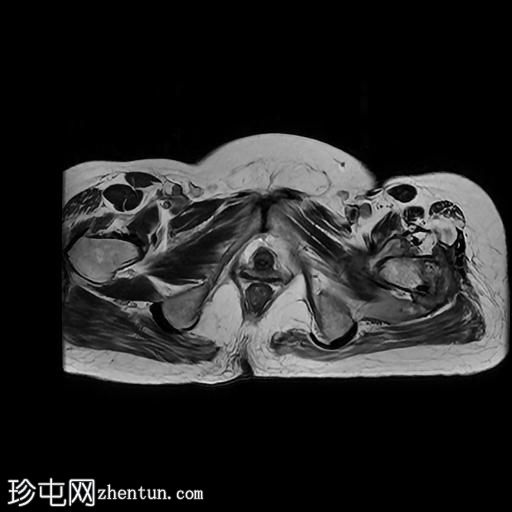

MRI

3.jpg

冠状位

T1加权像

左髋关节存在严重的关节病变,表现为关节间隙显著变窄、软骨丢失、软骨下骨髓水肿以及囊性改变。

此外,左股骨颈基底部、股骨粗隆间区及股骨大转子区域可见骨髓信号异常及皮质破坏。伴有滑膜增厚及较大的冷脓肿腔,提示左股骨颈及股骨粗隆间区骨髓炎。

另一处较大的冷脓肿从股骨受损部位开始向上延伸至左侧臀肌。

在左侧股骨外侧皮下可见低信号窦道。